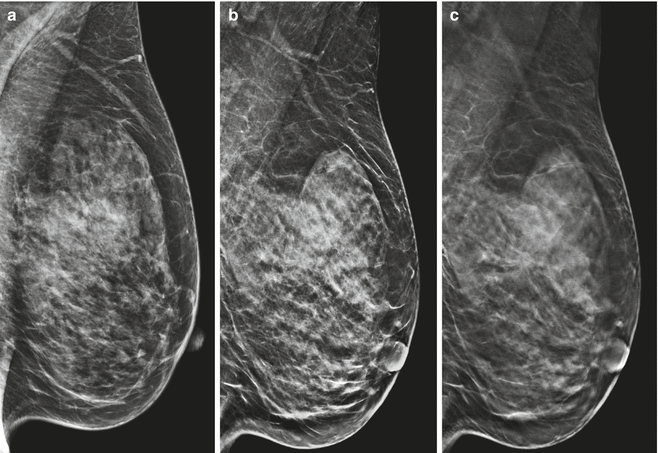

When using C-View software program, the tomosynthesis learning and reconstruction is performed in the standard manner. This can be cooked in any desirable projection. Following the reconstruction, an algorithmic program converts the 3D data into letter a single 2D C-View image (Figure 1). The radiologist is presented with some the C-View nonnegative 3D images.

When using C-View software, the tomosynthesis acquisition and reconstruction is performed in the standard manner. This can be done in any desired projection. Following the reconstruction, an algorithm converts the 3D data into a single 2D C-View image (Figure 1).

The radiologist is presented with both the C-View plus 3D images. Use of C-View images in clinical practice In our practice, we find that the C-View 2D image can be used in the same way as an acquired 2D image is used, as part of a 3D examination.